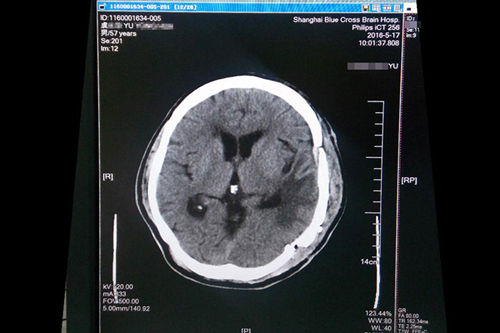

2016年4月,浙江寧波人,57歲的虞文軍(化名)因巨大腦腫瘤(8*6cm) 前來(lái)上海藍(lán)十字腦科醫(yī)院就診。經(jīng)包括沈建康教授在內(nèi)的專(zhuān)家會(huì)診后,考慮到患者腦腫瘤巨大、腫瘤周邊血供豐富,手術(shù)指征明確,常規(guī)手術(shù)切除恐出血過(guò)多,增加手術(shù)風(fēng)險(xiǎn),決定術(shù)前先為虞文軍行“超選擇性全腦血管造影術(shù)+腦膜瘤供血?jiǎng)用}栓塞術(shù)”,對(duì)腫瘤供血?jiǎng)用}進(jìn)行栓塞,減少出血量,再全麻下行“左側(cè)顳底部巨大腦膜瘤切除術(shù)”。沈教授已經(jīng)有十年未見(jiàn)過(guò)患者有如此大的腫瘤,患者術(shù)后隨即恢復(fù)清醒,自我感覺(jué)頭腦較前更清醒,語(yǔ)音、語(yǔ)速恢復(fù)較好,不到半個(gè)月便已能正常行走,順利出院。

沈建康教授為虞文軍成功施行巨大腫瘤切除術(shù)

術(shù)前磁共振影像顯示巨大腦腫瘤

術(shù)后一個(gè)月復(fù)查CT影像顯示恢復(fù)良好